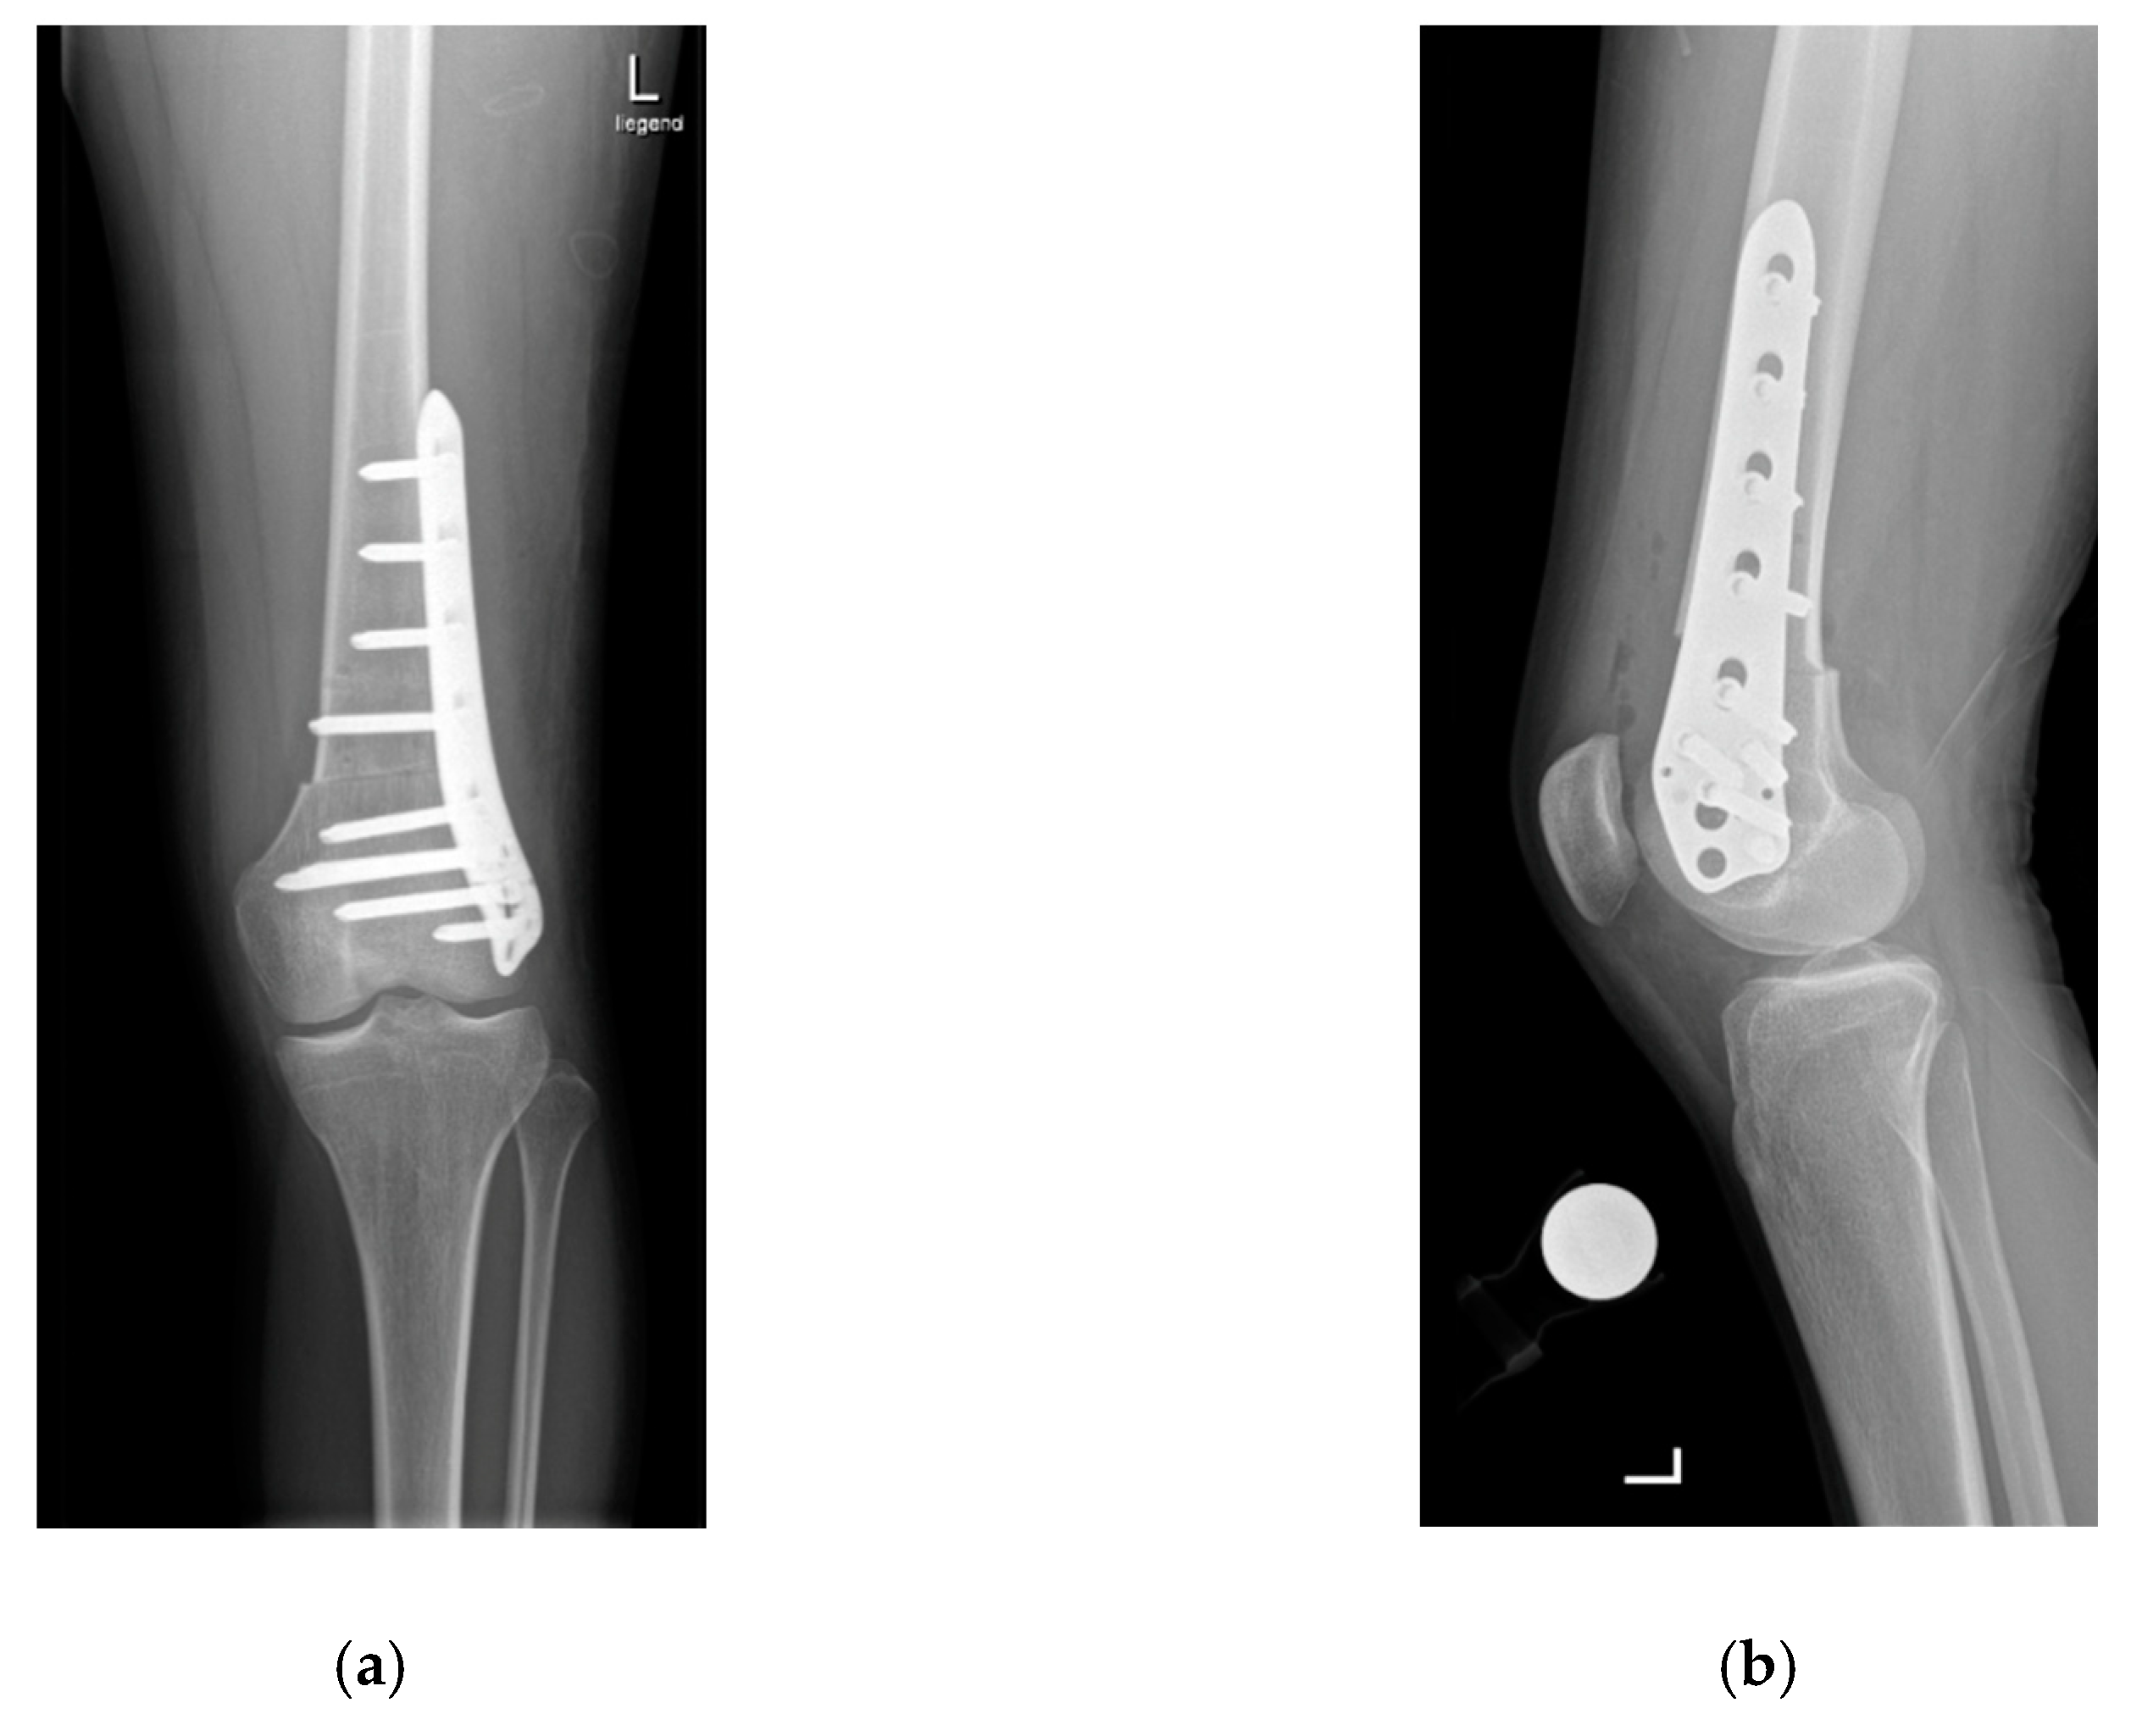

A lateral subvastus approach is used for the supracondylar osteotomies [1,7,12]. Two Kirschner wires are placed anteriorly 3–5 cm above the metaphysis to monitor the planned angle of correction. The osteotomy is performed horizontally with an oscillating saw and then the distal femur is externally rotated to correct the increased internal rotation until the two Kirschner wires are positioned as the preoperative planning has indicated. Fixation of the osteotomy is performed using a locking screw osteosynthesis plate (Figure 2a,b).

Figure 2.

Anteroposterior (a) and sagittal (b) radiographs showing the situation after supracondylar rotational osteotomy.